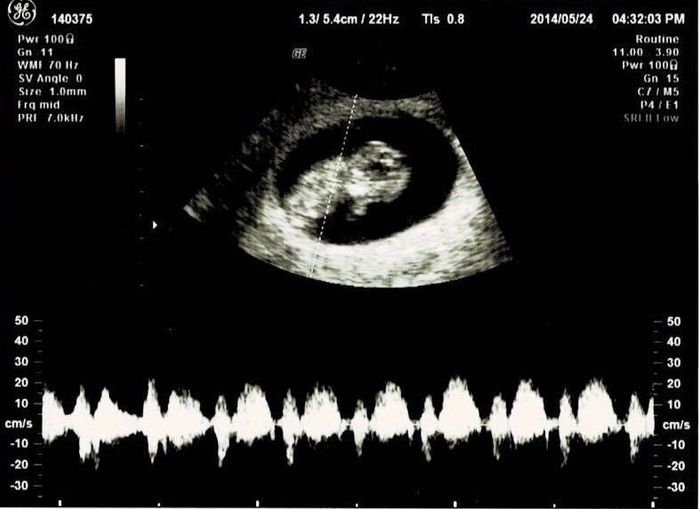

妊娠12週目エコー写真

つわり真っ盛り。しかし、おなかはまだ大きくありません。この日は採血をして、麻疹、風疹などの抗体があるか、梅毒の反応がないかなどの妊娠前期検査をしてもらいました。赤ちゃんはきちんと手足が見えて驚きました。さらには背骨まで確認できました。改めておなかの中に人間がいるという感慨がわいて、不思議な気持ちに。ガイコツみたいなエコーでもかわいいと感じました。